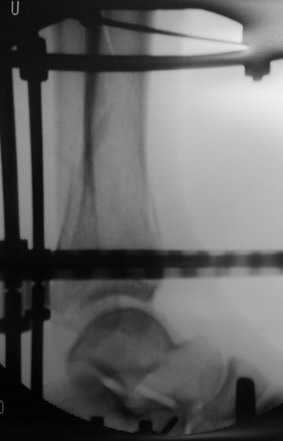

Пример - довольно похожий перелом, оперированный в первые 8 часов после аварии у 40-летнего больного, страдающего тяжёлым сахарным диабетом 1 типа.